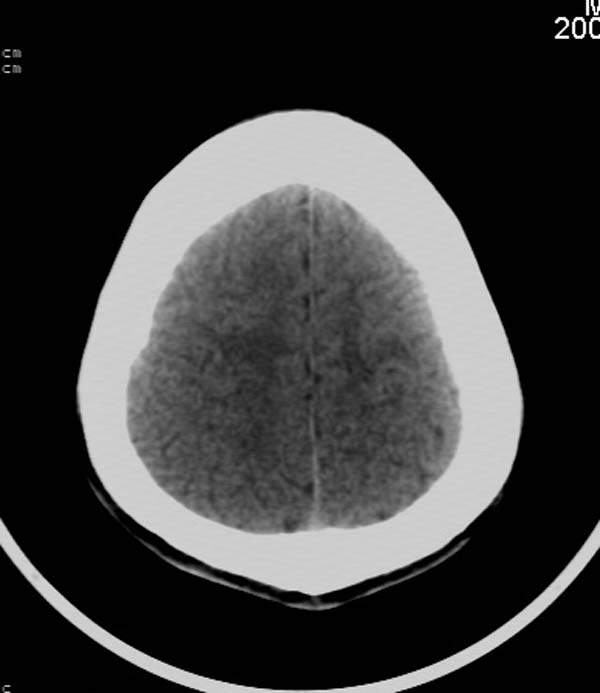

患者,男,24岁。头面部外伤后意识障碍1小时。

小脑幕缘密度增高,考虑有少量出血,建议复查

考虑右侧天幕缘少量蛛网膜下腔出血;建议:必要时复查。

1)考虑少量蛛网膜下腔出血;建议:必要时复查。2)桥前池及左侧环池表皮样囊肿可能。建议:行mri检查。

考虑右侧天幕缘区域少量蛛网膜下腔出血。

当ct表现不明显,临床症状相当明显时,建议mri+dwi序列除外弥漫性轴索损伤之可能。

一侧密度增高,是否考虑为硬膜下血肿,前额血肿真好对冲伤,桥小脑脚增宽建议进一步检查